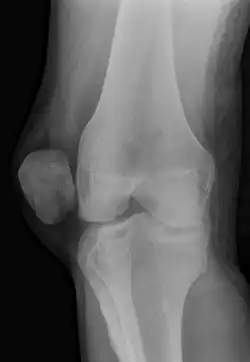

Patellar dislocation

To assess the knee, a clinician can perform the Patellar Aprehension Test by moving the patella back and forth while the people flexes the knee at approximately 30 degrees.[14]

The people can do the patella tracking assessment by making a single leg squat and standing, or by lying on his or her back with knee extended from flexed position. A patella that slips laterally on early flexion is called the J sign, and indicates imbalance between the VMO and lateral structures.[15]

On X-ray, with skyline projections, dislocations are readily diagnosed. In borderline cases of subluxation, the following measurements can be helpful: